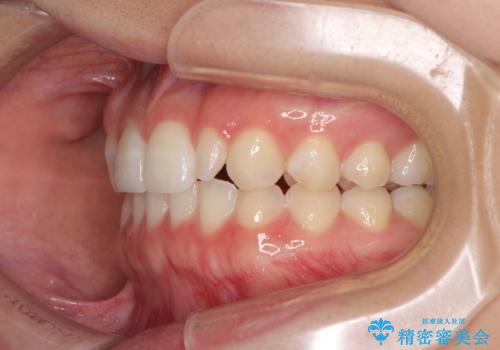

海外転居前に気になる前歯を整えたい 上下前歯の部分矯正

- 1年後に海外に転居するため、気になる前歯を矯正治療で整えたいとのことで来院された患者様です。

下顎は叢生が強かったため、奥歯までワイヤーを装着し、上顎は前歯の一部のみ気になっていたので、その部分にだけワイヤー装置を装着することとしました。